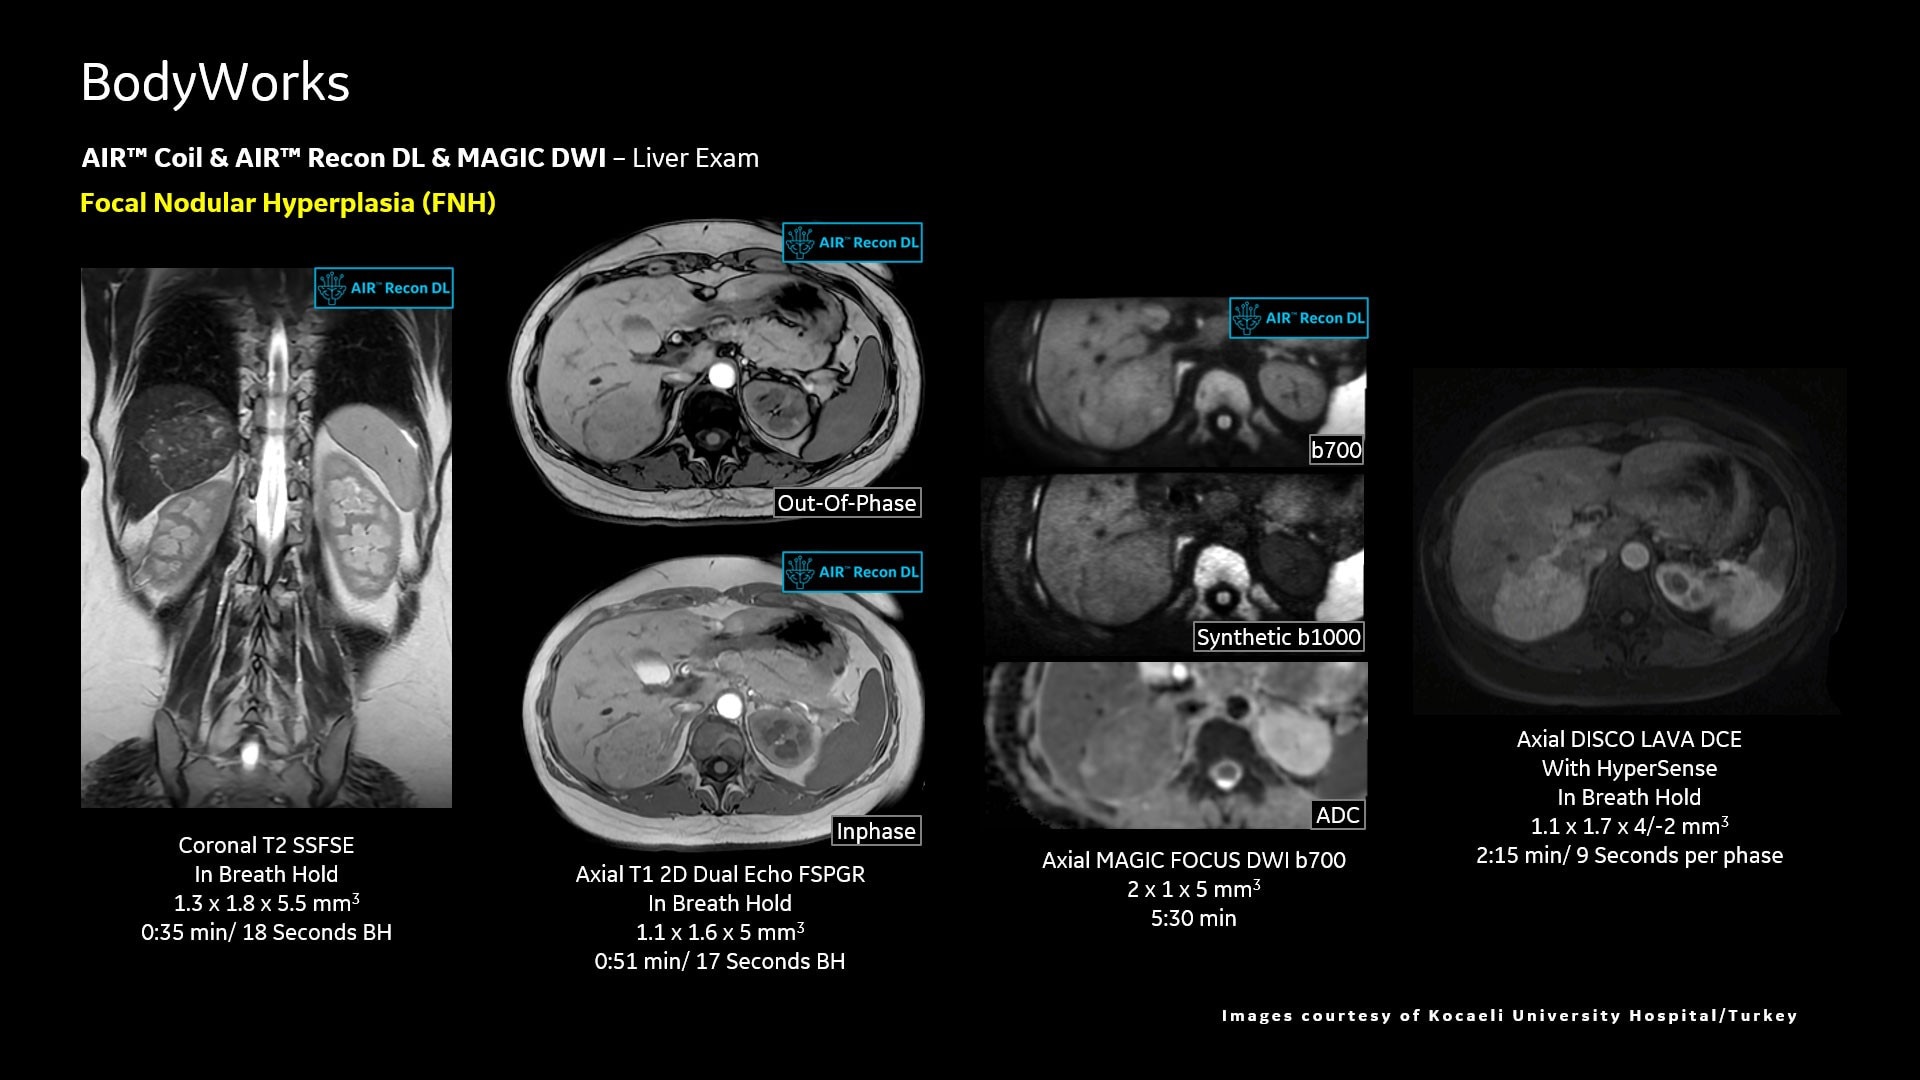

AIR™ Recon DL improves SNR and image sharpness, enabling shorter scan times

Up to 50% faster acquisition time with AIR™ Recon DL

Achieve a 25% efficiency gain with Ultra High Efficiency (UHE) gradient system. Fast, clear Total Digital Imaging (TDI) increases SNR by 25%. Improved IQ in 80% of cases without added time. Acquire higher SNR without a time penalty and get images virtually free of artifact with AIR™ Recon DL.***